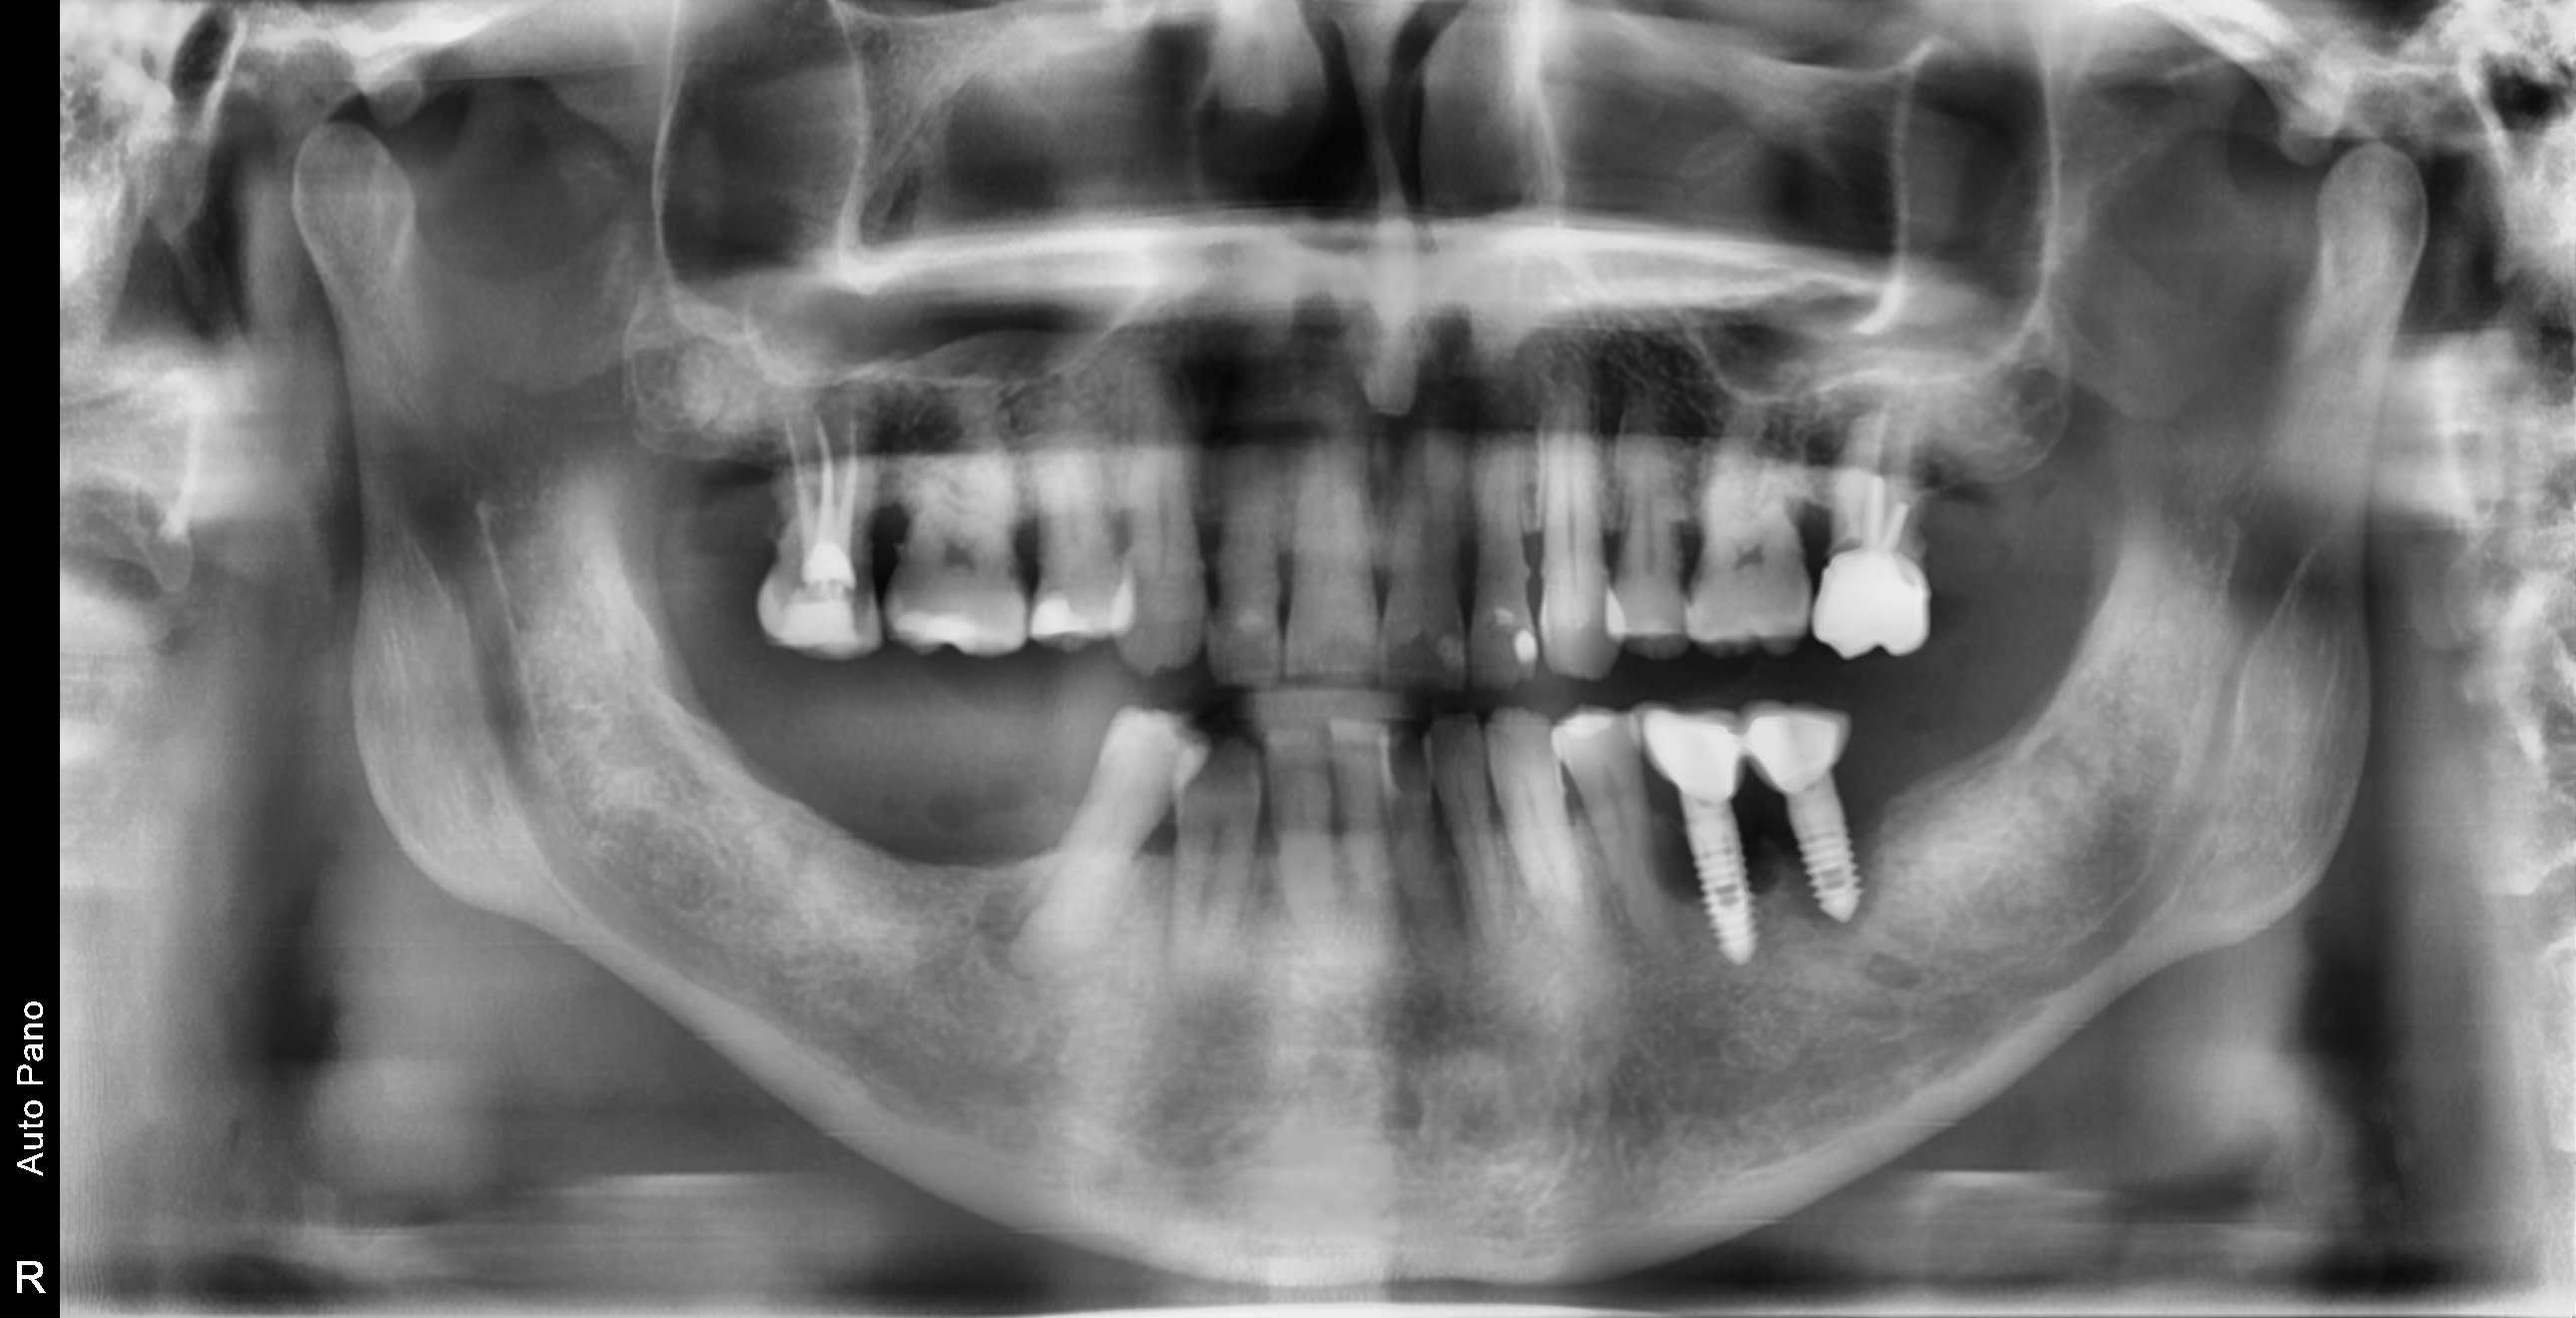

Je cherche à identifier les implants des 2 cas ci-dessous: l'une rétrolavéolaire et l'autre je n'ai que la pano pour le moment

Sur la pano, est-ce bien nécessaire de les identifier…..pour moi c’est tourne à gauche et bassinet….